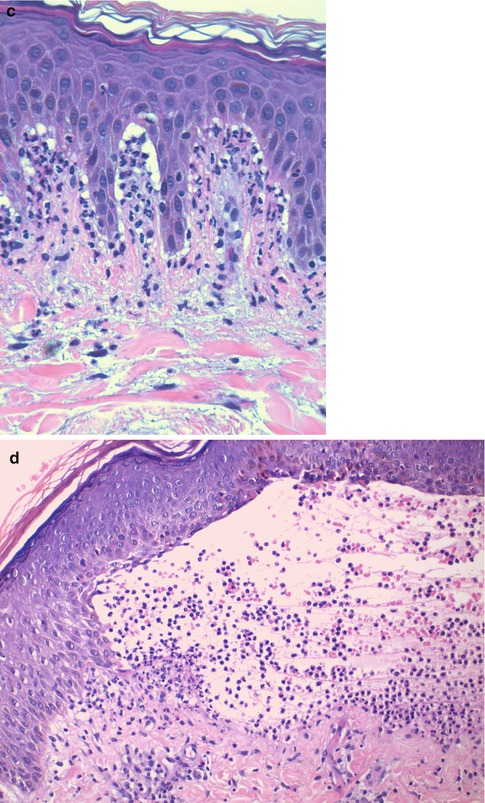

Fig. 16.2

(a) Pemphigus vulgaris. Intraepidermal blister located suprabasally with acantholytic cells floating inside the vesicle. The cells of the basal layer remain attached to the basement membrane zone showing a characteristic row of tombstone pattern (hematoxylin-eosin stain; original magnification ×200). (b) Pemphigus vegetans. Acanthosis and pseudoepitheliomatous hyperplasia together with suprabasal clefting and prominent acantholysis (hematoxylin-eosin stain; original magnification ×100). (c) Pemphigus foliaceus. Intraepidermal blister located within the stratum corneum (subcorneal) with some acantholytic cells floating inside the vesicle (hematoxylin-eosin stain; original magnification ×200). (d) Pemphigus foliaceus. There is no evident intraepidermal blister. The clues for diagnosis are the absence of stratum corneum and granulosum and the presence of neutrophilic spongiosis (epidermal spongiosis with presence of neutrophils) (hematoxylin-eosin stain; original magnification ×200). (e) Paraneoplastic pemphigus. There is no acantholysis. The biopsy shows a prominent lichenoid dermatitis with several necrotic keratinocytes and basement membrane vacuolization. This patient had an associated follicle center lymphoma (hematoxylin-eosin stain; original magnification ×200). (f) IgA pemphigus of the subcorneal pustular dermatosis subtype. Subcorneal pustule with abundant neutrophils and superficial epidermal spongiosis (hematoxylin-eosin stain; original magnification ×40)

The histopathological findings in endemic and non-endemic pemphigus foliaceus (PF), pemphigus erythematosus, and drug-induced cases of pemphigus are identical. They are characterized by the presence of superficial acantholysis, just below the granular layer of the epidermis (Fig. 16.2c). Initial vesicles can contain abundant neutrophils or eosinophils. Occasionally, as a result of the blisters having a very thin ceiling, they break and loose the upper layer. This may give the appearance of a “normal epidermis” or even of a psoriasiform dermatitis, with no clear finding of acantholysis. The clue for diagnosis in these cases is the absence of stratum corneum and parts of the stratum granulosum (Fig. 16.2d) [5]. The main differential diagnosis here is with impetigo and staphylococcal scalded skin syndrome that are both disorders caused by the cleavage of the extracellular domain of desmoglein 1 by a toxin produced by certain strains of Staphylococcus aureus.